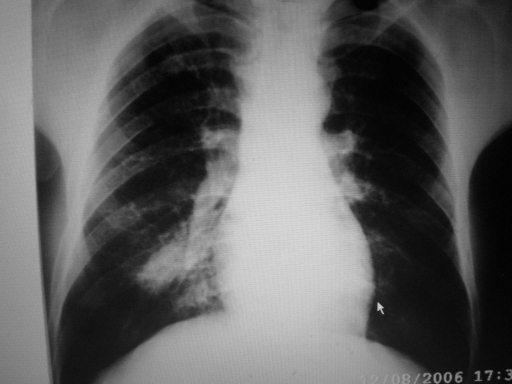

男,44,胸痛,咳嗽月余。

考虑周围型肺癌

支持典型的周围型肺癌,该有的都有了。

浮云掩月征

是肺癌所致阻塞性肺炎的特征性x线征象,多见于周围型肺癌。当癌肿在支气管腔内生长到一定程度时,管腔狭窄或阻塞,引起阻塞性肺炎。在胸部x线相上呈密度较淡的云絮状阴影。如果肿块同时向管腔外生长,则出现较浓的肿块阴影。当两者投影连成一片时,在云絮状阴影肿隐约可见一密度较浓的肿块阴影,宛如浮云掩月一样,故称为浮云掩月征。

胸片上病灶成条柱状,ct病灶内见钙化影,可见分叶与毛刺和胸膜凹陷征,考虑1感染病变[结核或炎性假瘤]。2肺癌。建议结合临床及进一步检查[如穿刺活检]

右肺下叶内野高密度影,边缘欠清.

考虑1 右下肺感染,建议疗后复查

2 右下肺周围型肺癌